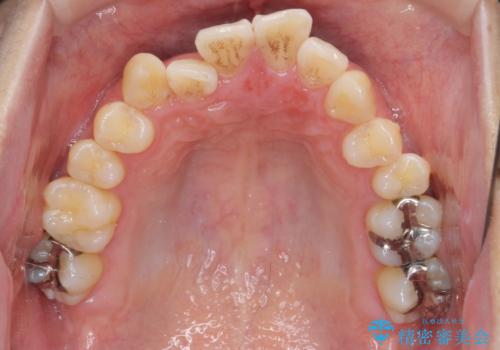

ねじれ・がたつきのある前歯を改善

- がたつき・すれ違い、ねじれのある前歯の見た目、噛み合わせの改善を希望され来院されました。

4本の小臼歯抜歯を避け、下顎前歯の1本抜歯の極力少ない抜歯本数で審美的な歯並びを得る治療計画としました。